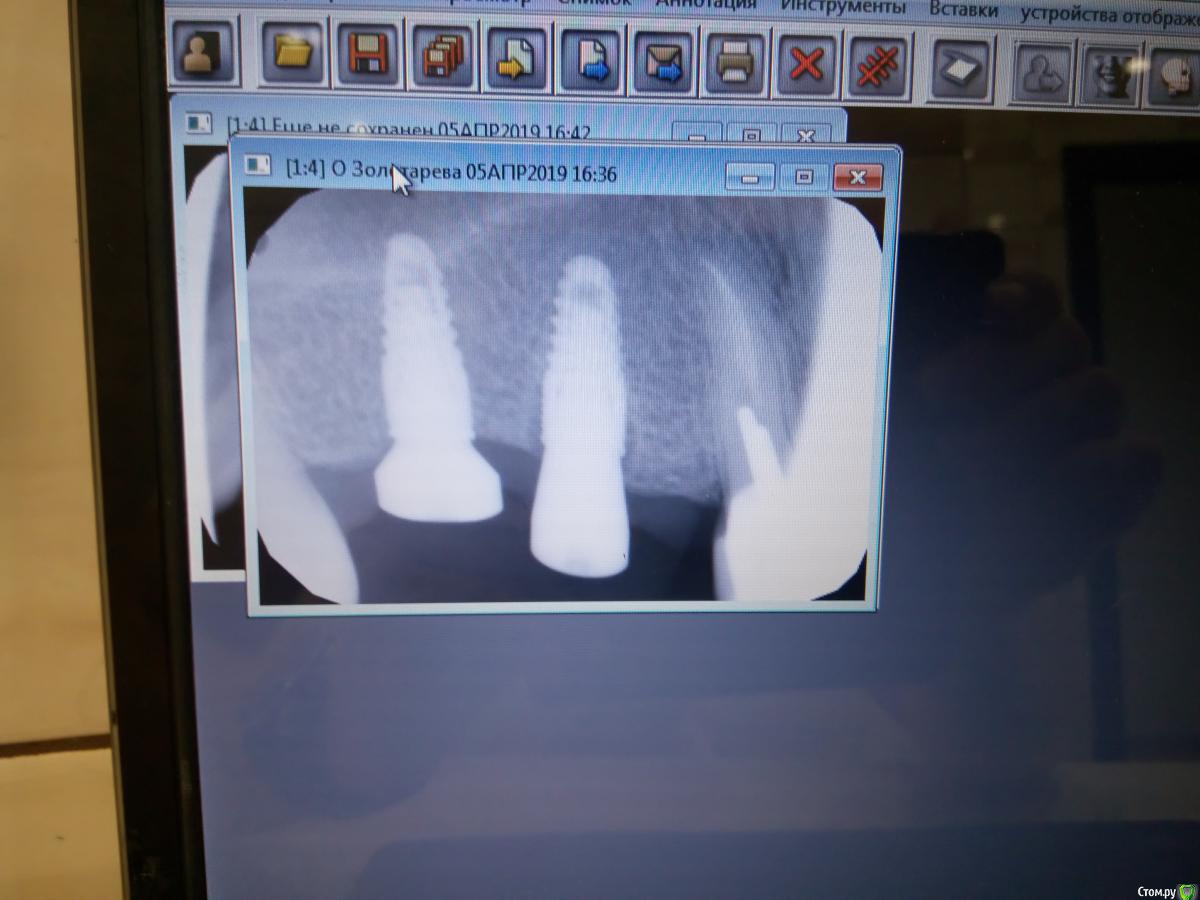

zubovolok Опубликовано 5 апреля, 2019 Поделиться Опубликовано 5 апреля, 2019 Коллеги 5 месяцев назад устанавливал импланты в позиции 1.6 и 1.5, в области шейки 1.5 деструкция кости, сегодня устанавливал фдм, жалоб никаких не было. Как быть в такой ситуации? Ссылка на комментарий

Smileee Опубликовано 5 апреля, 2019 Поделиться Опубликовано 5 апреля, 2019 Видел похожую ситуацию у коллеги. Он сделал так: подсадил ССТ с бугра на ФДМе и затем запротезировал. Через год, на контрольном снимке кость полностью восстановилась и стала вровень с имплантатом. Ссылка на комментарий